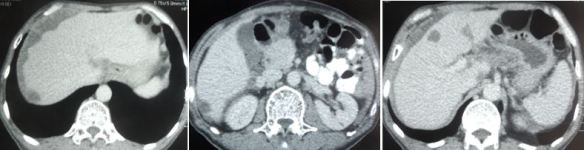

CT scan showed:

- An irregular mass in the distal segment of ascending colon, measuring 4.1 x 1 cm and it is 8.6 cm long. There is narrowing of the colonic lumen.

- There is pericolonic tumour infiltration and the lymph nodes are mildly enlarged.

- There are two small metastatic liver nodules measuring 1.3 cm and 1.4 cm.